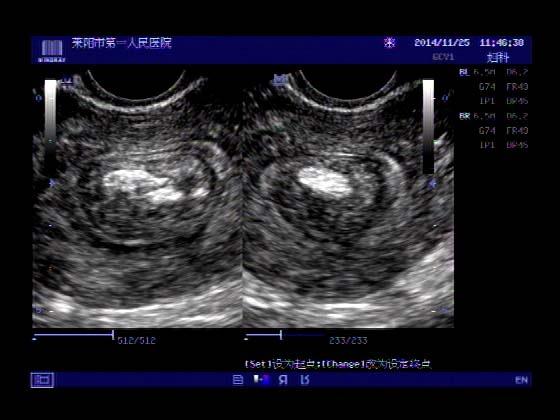

超声入门贴379---------粘膜下肌瘤(阴超的魅力)

女,43岁,月经量多3个多月,加重一个月

外院彩超检查提示:子宫后肌壁略高回声团------肌瘤?息肉?,盆腔少量积液

今天来我院检查:

巧妇难为无米之炊,经腹部超声确实很难定,阴超一目了然,乡镇医院诊断水平的提高更迫切的需要高档仪器的引进!